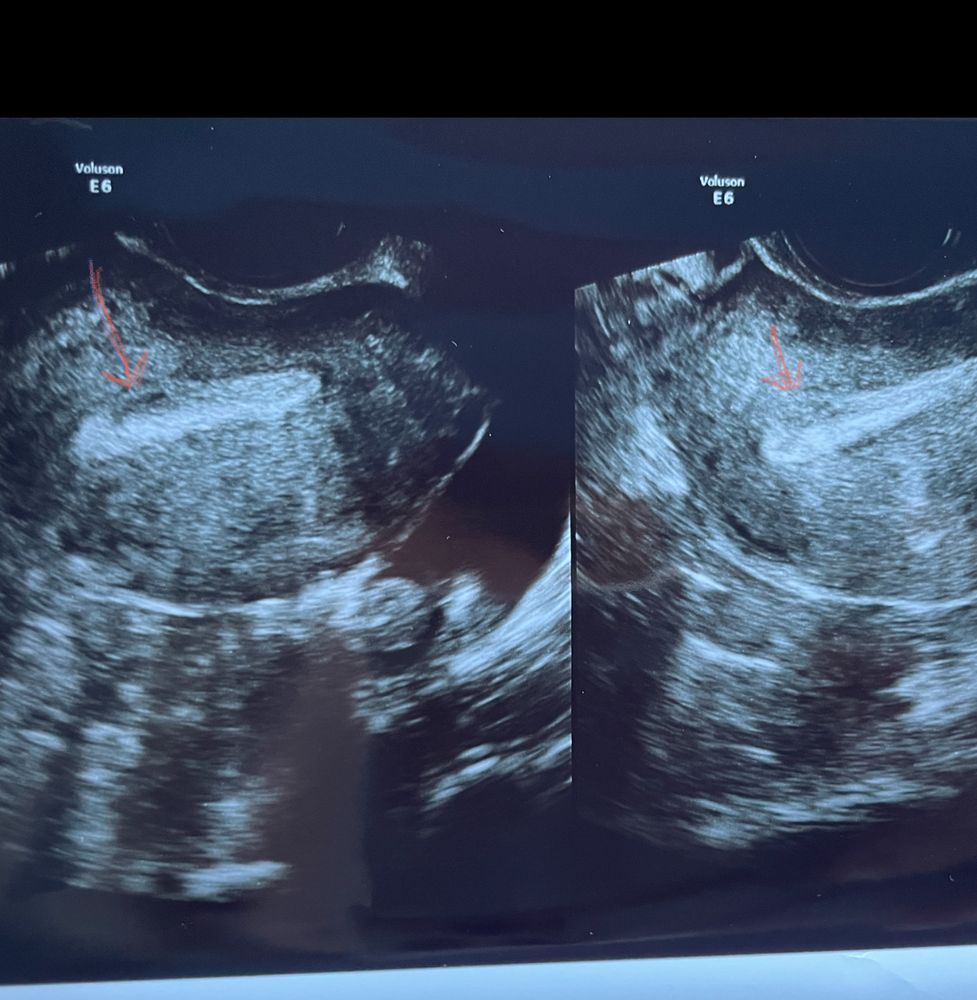

Девочки что это может быть на узи в эндометрии?

Счастье очень близко , у меня неделю назад было эко! Уж полип бы точно заметили. Эта Белая полоска на узи всё эндометрий, во второй фазе он становится белым и монолитным от прогестерона. Я проверяю почти каждый цикл, но вот такого темного места раньше не видела. Спрашиваю о нём

Счастье очень близко , мне тоже напоминает какой то нарост, эндометрий в этом месте неоднородный.

Вообще у меня лично так выглядит шов после кесарево сечение

Nessik, но вот эта белая полоса это и есть шов от КС

Елена , эта белая полоса это сам эндометрий